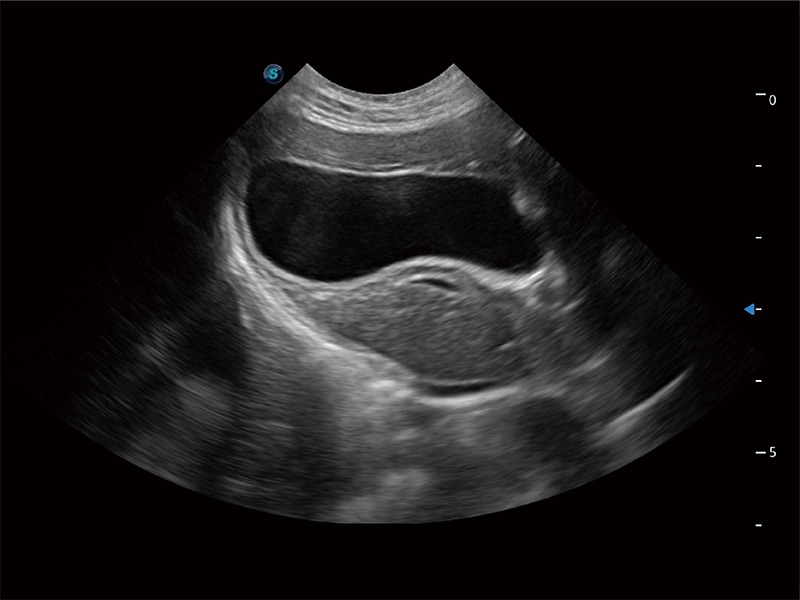

ProPet 80 配备了丰富的心脏探头群、先进的成像技术和专业的心脏测量工具,可帮助动物医生为不同体型和生理结构的动物提供心脏和心肌功能的全面评估。

ProPet 80 专为动物医生设计,对不同的动物体型和生理结构作出了针对性的优化。通过动物影像专用软件,可满足个性化的应用需求,帮助动物医生获得更精确的诊断数据。